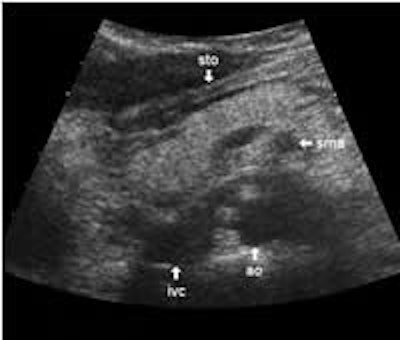

The following study describes anatomical landmarks in the ordinary pancreas of a thin patient:

Transverse planes in caudal direction:

More or less fat tissue can be seen separating the pancreas from the following structures: The head and body of the pancreas are located below the liver, and below and generally behind the distal part of the stomach. The pancreatic head and body are located in front of the inferior vena cava and the aorta with the celiac trunk. To the far left, the tail of the pancreas has a position below the spleen and above the left kidney.

The dorsal aspect of the head takes the shape of a hook surrounding the right side of the superior mesenteric vein; the sharp left-pointing tip of the hook behind the vein constitutes the uncinate process. The splenic vein runs from the left along the dorsal border of the tail and body to the superior mesenteric vein, where these veins join to form the portal vein behind the "neck" of the pancreas. The portal vein then leaves the pancreas to the right and slightly upwards and runs into the liver hilum.